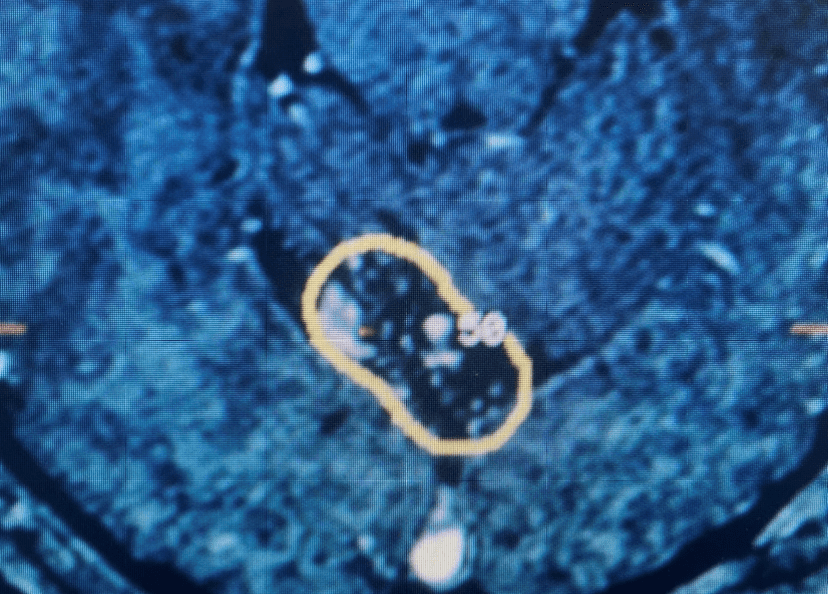

Figure 2. Axial T2 MRI of the lumbar spine demonstrating L2-3 stenosis due to significant facet arthropathy.